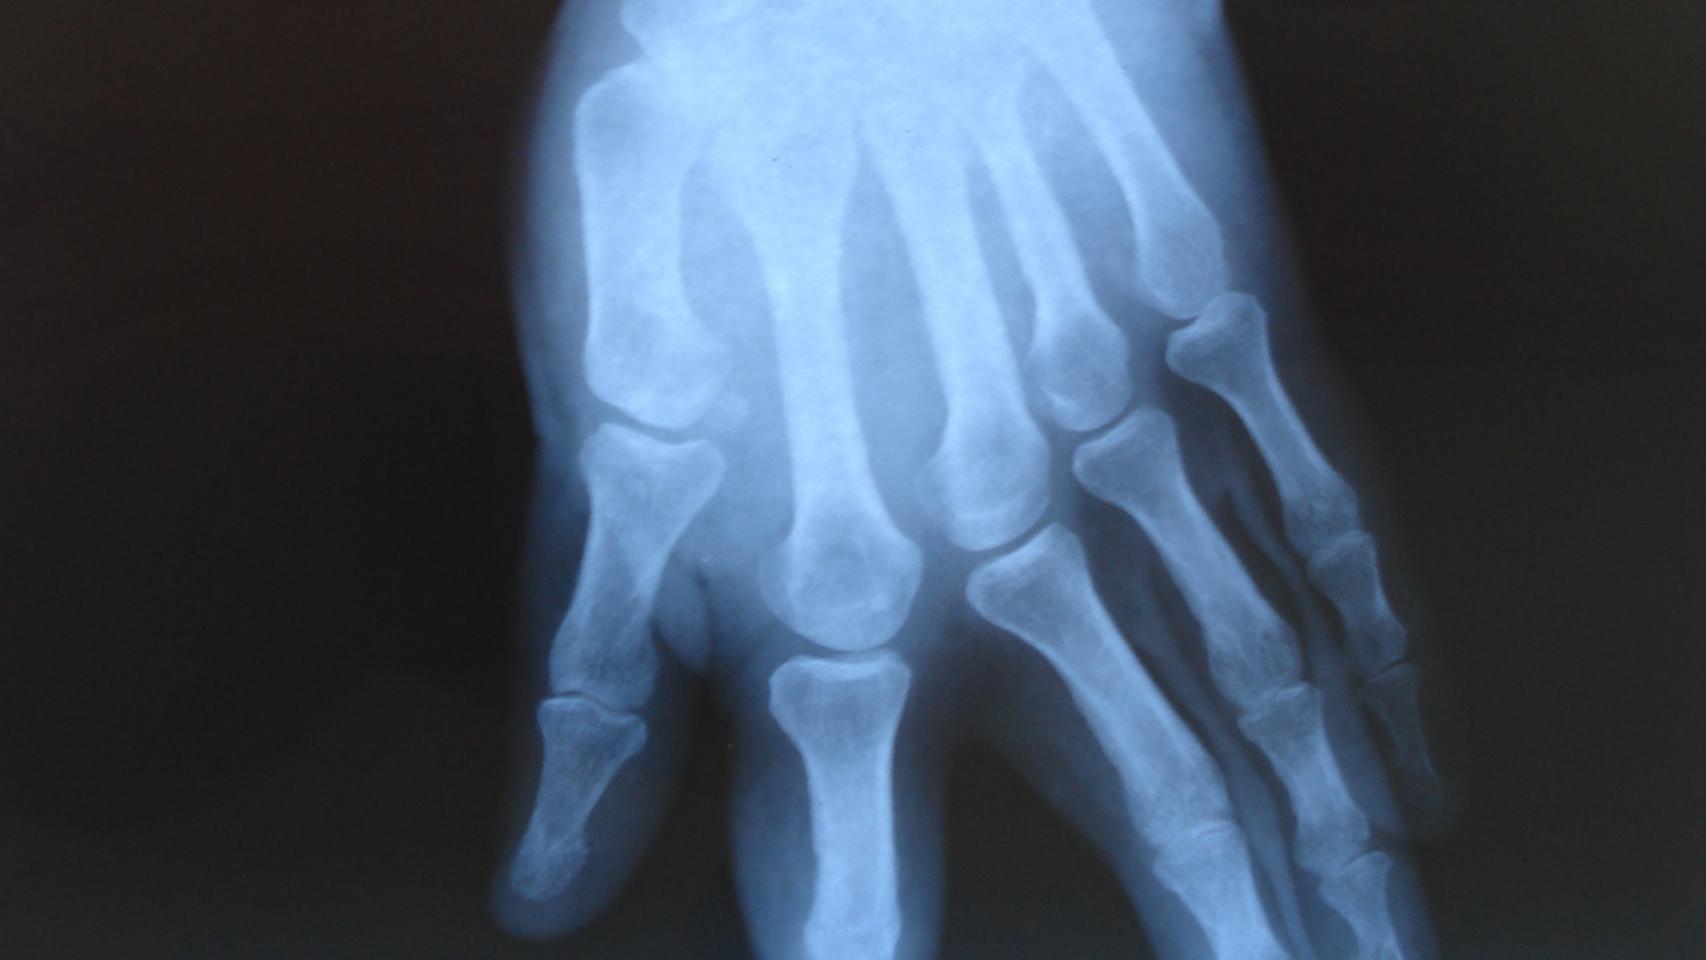

Una radiografía de la mano izquierda de Rafael

Una radiografía de la mano izquierda de Rafael Cedida

La inquietud acechó desde el primer momento a la familia. El primer informe médico data del 8 de abril de 1965, un mes y dos días después de su nacimiento. Era apenas un diagnóstico, un esquema de lo que Rafael y sus padres no supieron hasta varias décadas después. “Auscultación de cúbito y radio izquierdo. Este niño tiene el codo derecho rígido, sin ninguna movilidad. La extremidad superior izquierda tiene agenesia de radio y el cúbito unido al húmero, estando la mano rotada 180”. Los médicos calificaron aquello como una “malformación congénita de extremidades superiores”.